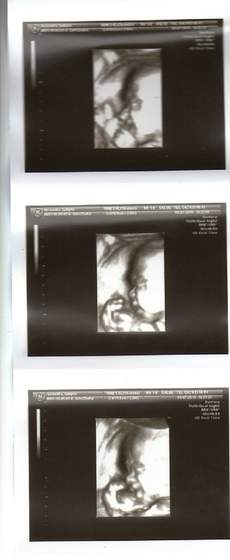

Zdjęcia USG Naszych dzieciątek :)))

Alanek z dziś. 23 tygodnie i 6 dni.

Bombusia... Twoje maleństwo wygląda idealnie:) jakby już się miało urodzić, tak fajnie buźkę widać:P

Bombusia ale fajny "pączuszek",urzekly mnie te pyzate poliki.super.